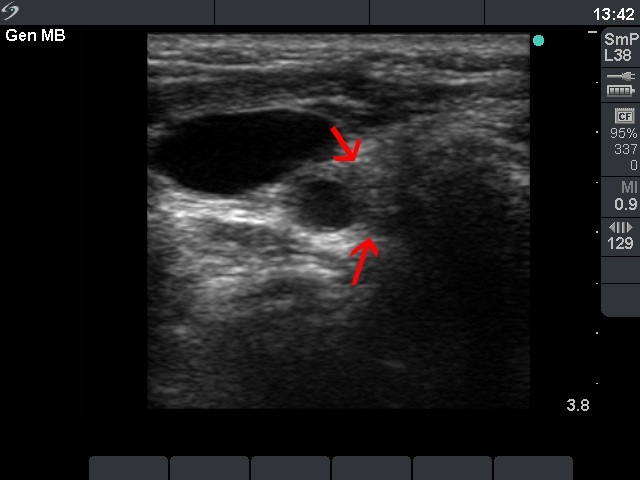

Right lobe, horizontal view

Right lobe, transverse scan. The inconspicuous, moderately hypoechogenic lesion is signed with red arrows.